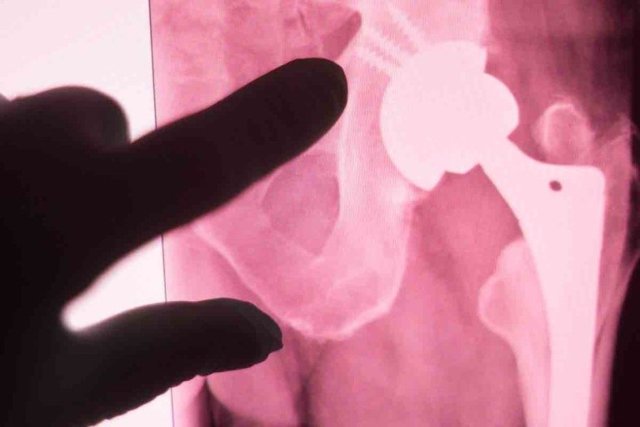

نتایج بررسی اشعه ایکس از فرآیند ترمیم استخوانهای شکسته نشان داد که سرامیک مورد استفاده در ایمپلنت جدید پس از گذشت فرایند درمان به استخوان تبدیل میشود.